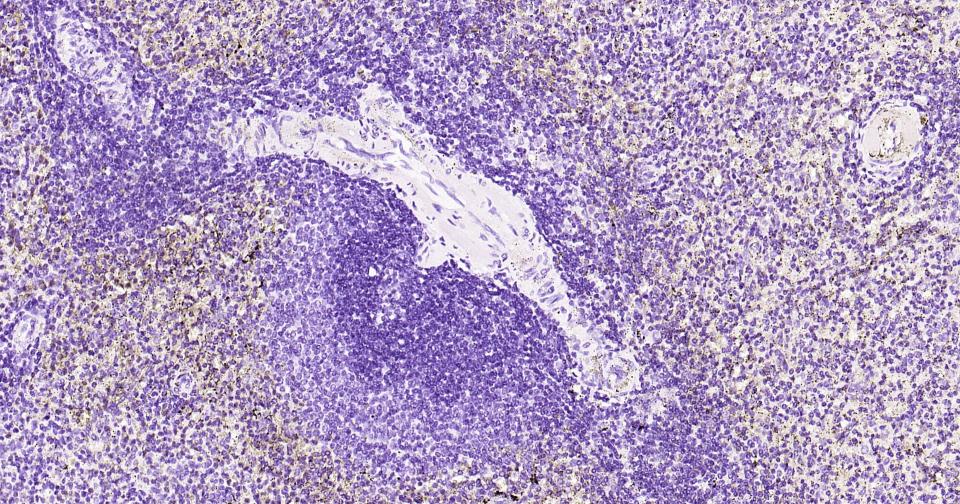

(Negative control)Paraformaldehyde-fixed, paraffin embedded Rat Spleen; Antigen retrieval by boiling in sodium citrate buffer (pH6.0) for 15 min; Antibody incubation with Tau-4 Monoclonal Antibody, Unconjugated(bsm-41804M) at 1:600 overnight at 4°C, followed by conjugation to the SP Kit (Mouse, sp-0024) and DAB (C-0010) staining.

(Negative control)Paraformaldehyde-fixed, paraffin embedded Mouse Spleen; Antigen retrieval by boiling in sodium citrate buffer (pH6.0) for 15 min; Antibody incubation with Tau-4 Monoclonal Antibody, Unconjugated(bsm-41804M) at 1:600 overnight at 4°C, followed by conjugation to the SP Kit (Mouse, sp-0024) and DAB (C-0010) staining.

(Negative control) Paraformaldehyde-fixed, paraffin embedded Human Spleen; Antigen retrieval by boiling in sodium citrate buffer (pH6.0) for 15 min; Antibody incubation with Tau-4Monoclonal Antibody, Unconjugated(bsm-41804M) at 1:1000 overnight at 4°C, followed by conjugation to the SP Kit (Mouse, sp-0024) and DAB (C-0010) staining.